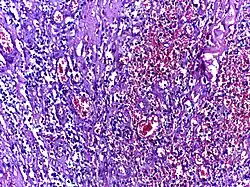

![]() |

Hodgkin's lymphoma | Micrograph of a lymph node in Hodgkin's lymphoma with the characteristic Reed-Sternberg cell. RS cell is a large cell with abundant amophophilic cytoplasm and binucleate mirror image nuclei. Each nucleus contains an acidophilic nucleolus surrounded by a halo. | Category: Histopathology of Hodgkin's lymphoma | Hodgkin's lymphoma |